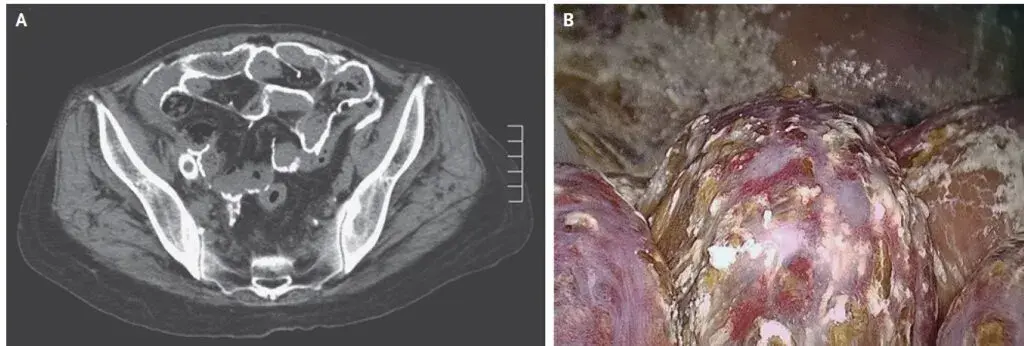

Realizado **TC de abdome** mostrou extensa calcificação do peritônio visceral e parietal (imagem A). Devido forte suspeita de **peritonite esclerosante encapsulante** foi realizado laparoscopia exploratória para confirmação diagnóstica. Pode-se observar um peritônio parietal muito espessado coberto por depósitos calcificados (imagem B). Aderências entre o peritônio e serosas inflamadas podem ser observadas.

O exame histopatológico mostrou fibrose e calcificação do peritônio parietal, sendo então confirmado o diagnóstico final de peritonite esclerosante encapsulante com extensa calcificações.